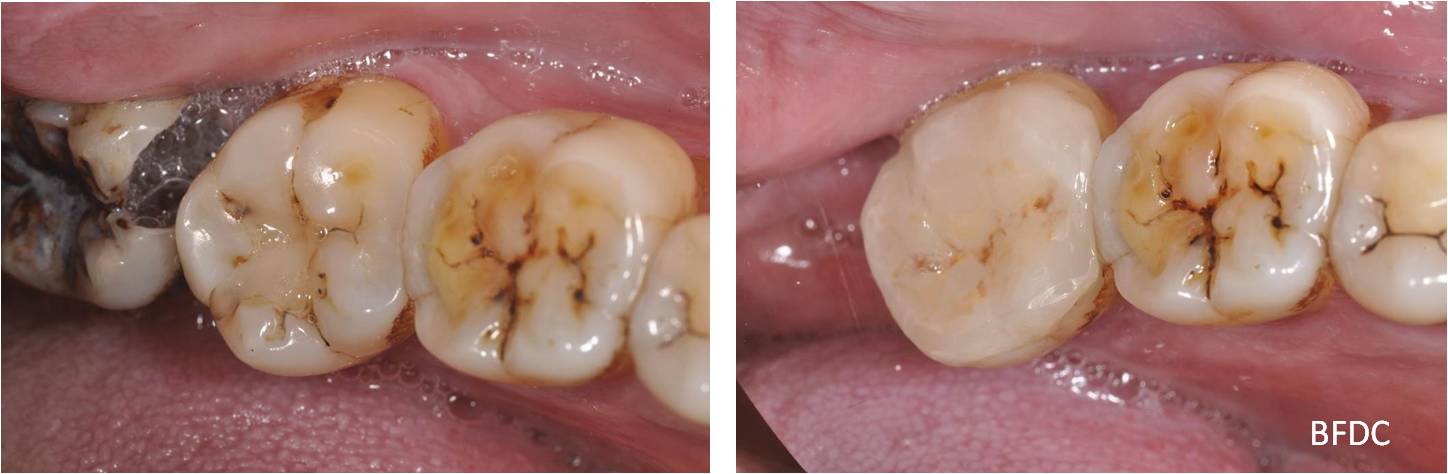

根管治療後陶瓷冠塊體-二次蛀牙-#37

根管治療

非手術根管治療